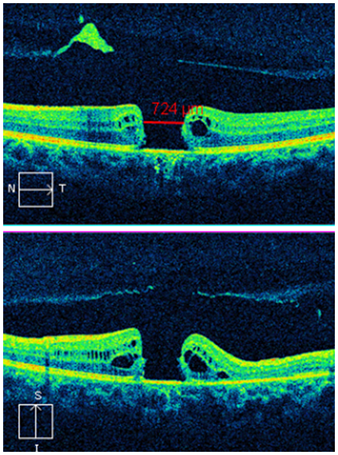

Anatomic closure of the macular hole was assessed by Macular OCT (Cirrus HD-OCT 400, Carl Zeiss Meditec, Inc. Germany) performed by one masked observer. Closure was defined when the entire circumference of the macular hole flattened against the retinal pigment epithelial layer (base-width). In this series FTMH closure was achieved in six of the seven patients after primary surgery (Figures 3&4).

Figure 3 Preoperative OCT of case 1 demonstrating 724 µm, full thickness macular hole.

Figure 4 Postoperative OCT of case 1 demonstrating closure of full thickness macular whole and minimal pigment epithelium thickening.

Case 1

The largest FTMH defect observed in this series was 724µm, observed in a 13 year old male. The patient had been struck by a soccer ball to the left eye, and had a period of 17 months from time of injury to surgery. Preoperative visual acuity was 6/36 in the left eye, and examination revealed a FTMH with no PVD, and extensive peripheral “leopard spotting” appearance consistent with previous commotio retinae. No other ocular injury was evident. Given the interval to surgery, the size of the hole and the absence of other injuries the retina expansion approach was used. At one week post-operatively the hole was noted to have closed. Follow up of the patient at routine intervals over the next 12 months demonstrated the hole had remained closed, and the final visual acuity was 6/24 in the left eye.